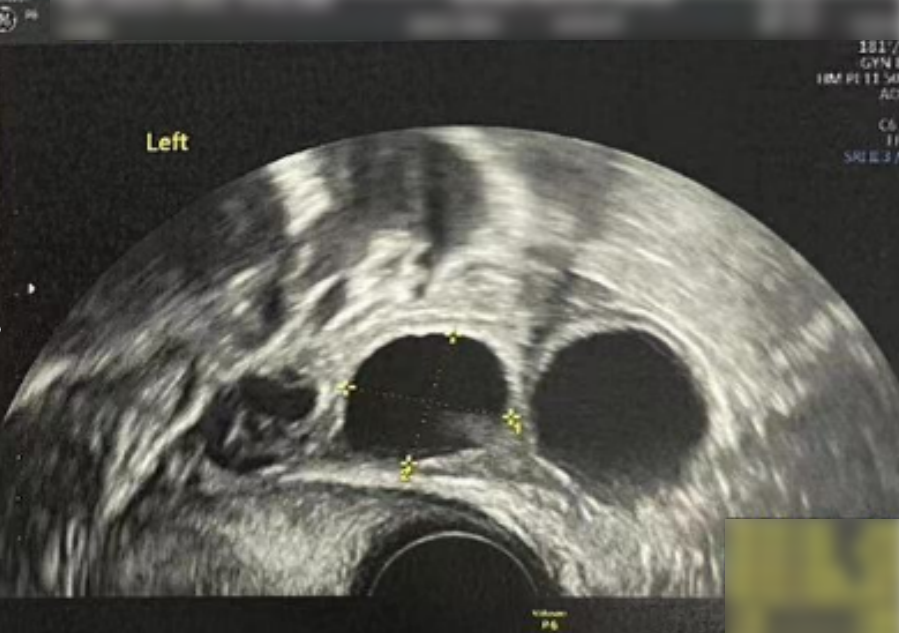

• 阴超检查:基础卵泡 6 颗

- 右侧卵泡 2 颗 (3-4mm)

- 左侧卵泡 4 颗 (3-5mm)

- 右侧卵泡 2 颗

- 左侧卵泡 6 颗

- 右侧卵泡 2 颗 (10,20mm)

- 左侧卵泡 5 颗 (20,18,12,7,7mm)